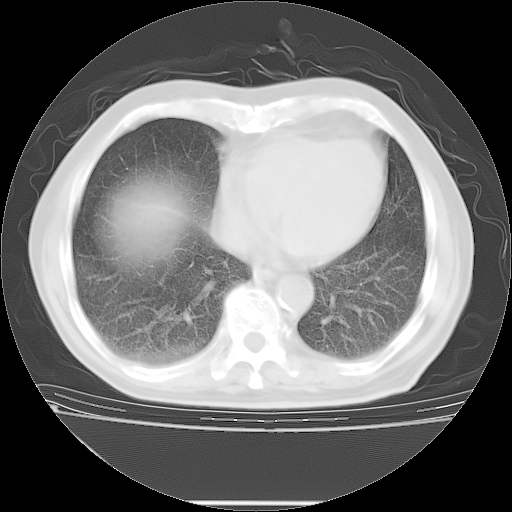

胸腹部CT,诊断意见:左上肺叶钙化灶、左侧胸膜局限性增厚并钙化、胆囊炎。描述部分肺组织呈磨玻璃样改变。

今天复查肺部CT,发现双肺广泛磨玻璃样改变。所以我把3月19日和5月9日相隔50天的肺部CT上传。请大家会诊。

2009年3月19日肺部CT片。

2009年3月19日肺部CT

大致读了系列胸部CT:纵隔窗无明显异常,肺窗:从4、27至今:主要是双肺中下野外带可见毛玻璃样改变,目前处于急性肺泡炎阶段,至于原因考虑1、结替组织或胶原血管性疾病所致?2、恶性疾病如恶组在肺部所致的表现或细支气管肺泡癌?3、药物或其它原因如肺蛋白沉着症所致肺泡炎目前不太可能?总之,明天就去请我院的呼吸科、感染科、血液科和临免专家会诊哈。